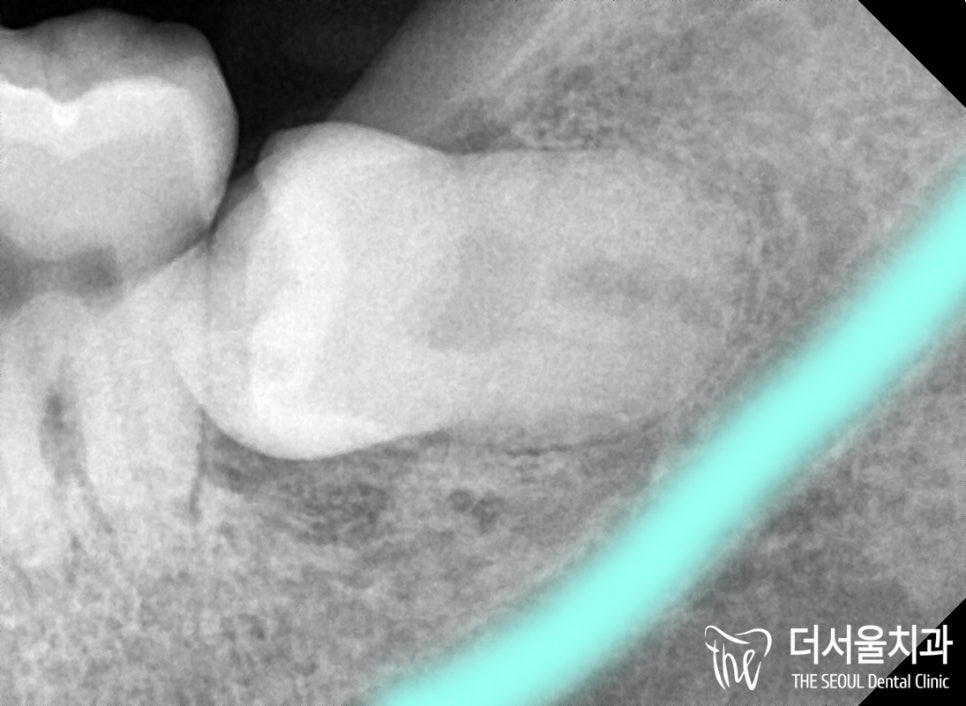

# 38번 매복 사랑니를 찾아낼 수 있었습니다.

완전히 옆으로 누워 숨어있었기에

잇몸 절개를 피할 수 없었는데요.

게다가 신경과 맞닿아있는 것은 아닌지

다행스럽게도 신경과

맞닿지 않은 거리였기에

발치를 진행할 수 있었습니다.

잇몸을 절개하여 열어봤을때,

깊숙히 숨어있는 것을 볼 수 있죠?

그런데 바로 뽑아내기엔

자리가 부족했었습니다.

그래서 조각내어 꺼낼 수밖에 없었는데요.